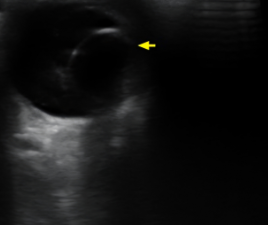

🩻 감가상각 대상 고가 장비 예시